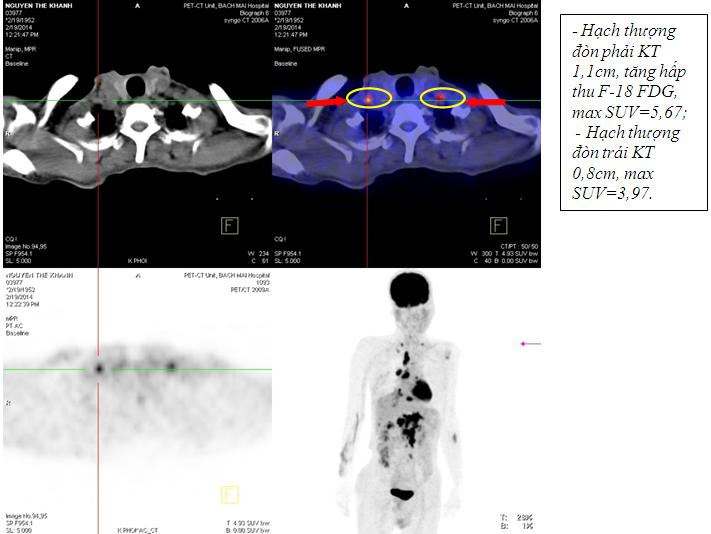

Kết quả chụp PET /CT

Kết quả chụp PET/CT: Khối vùng phế quản gốc phải KT 2,4x1,7cm; maxSUV=8,50; Hạch dưới carina KT 3,1x3,5cm ; maxSUV=8,50;Nhiều hạch ổ bụng dọc theo ĐMchủ bụng tạo thành khối lớn KT 8,5x5,1cm và 5,1x3,9cm, tăng hấp thu F-18 FDG, maxSUV=10,45; Hạch thượng đòn phải KT 1,1cm, tăng hấp thu F-18 FDG, max SUV=5,67; Hạch thượng đòn trái KT 0,8cm, max SUV=3,97; Tổn thương cung sau xương sườn số 2 bên phải tăng hấp thu F-18 FDG, max SUV=3,13; Nhu mô gan hạ phân thùy VI có nốt KT 1,2cm, tăng hấp thu F-18 FDG, max SUV=4,15.